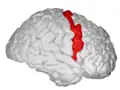

Precentral gyrus

Precentral gyrus a prominent gyrus of the frontal lobe

The precentral gyrus is a prominent gyrus on the surface of the posterior frontal lobe of the brain. It is the site of the primary motor cortex that in humans is cytoarchitecturally defined as Brodmann area 4.

The precentral gyrus lies in front of the postcentral gyrus - mostly on the lateral (convex) side of each cerebral hemisphere - from which it is separated by the central sulcus. Its anterior border is represented by the precentral sulcus, while inferiorly it borders to the lateral sulcus (Sylvian fissure). Medially, it is contiguous with the paracentral lobule.